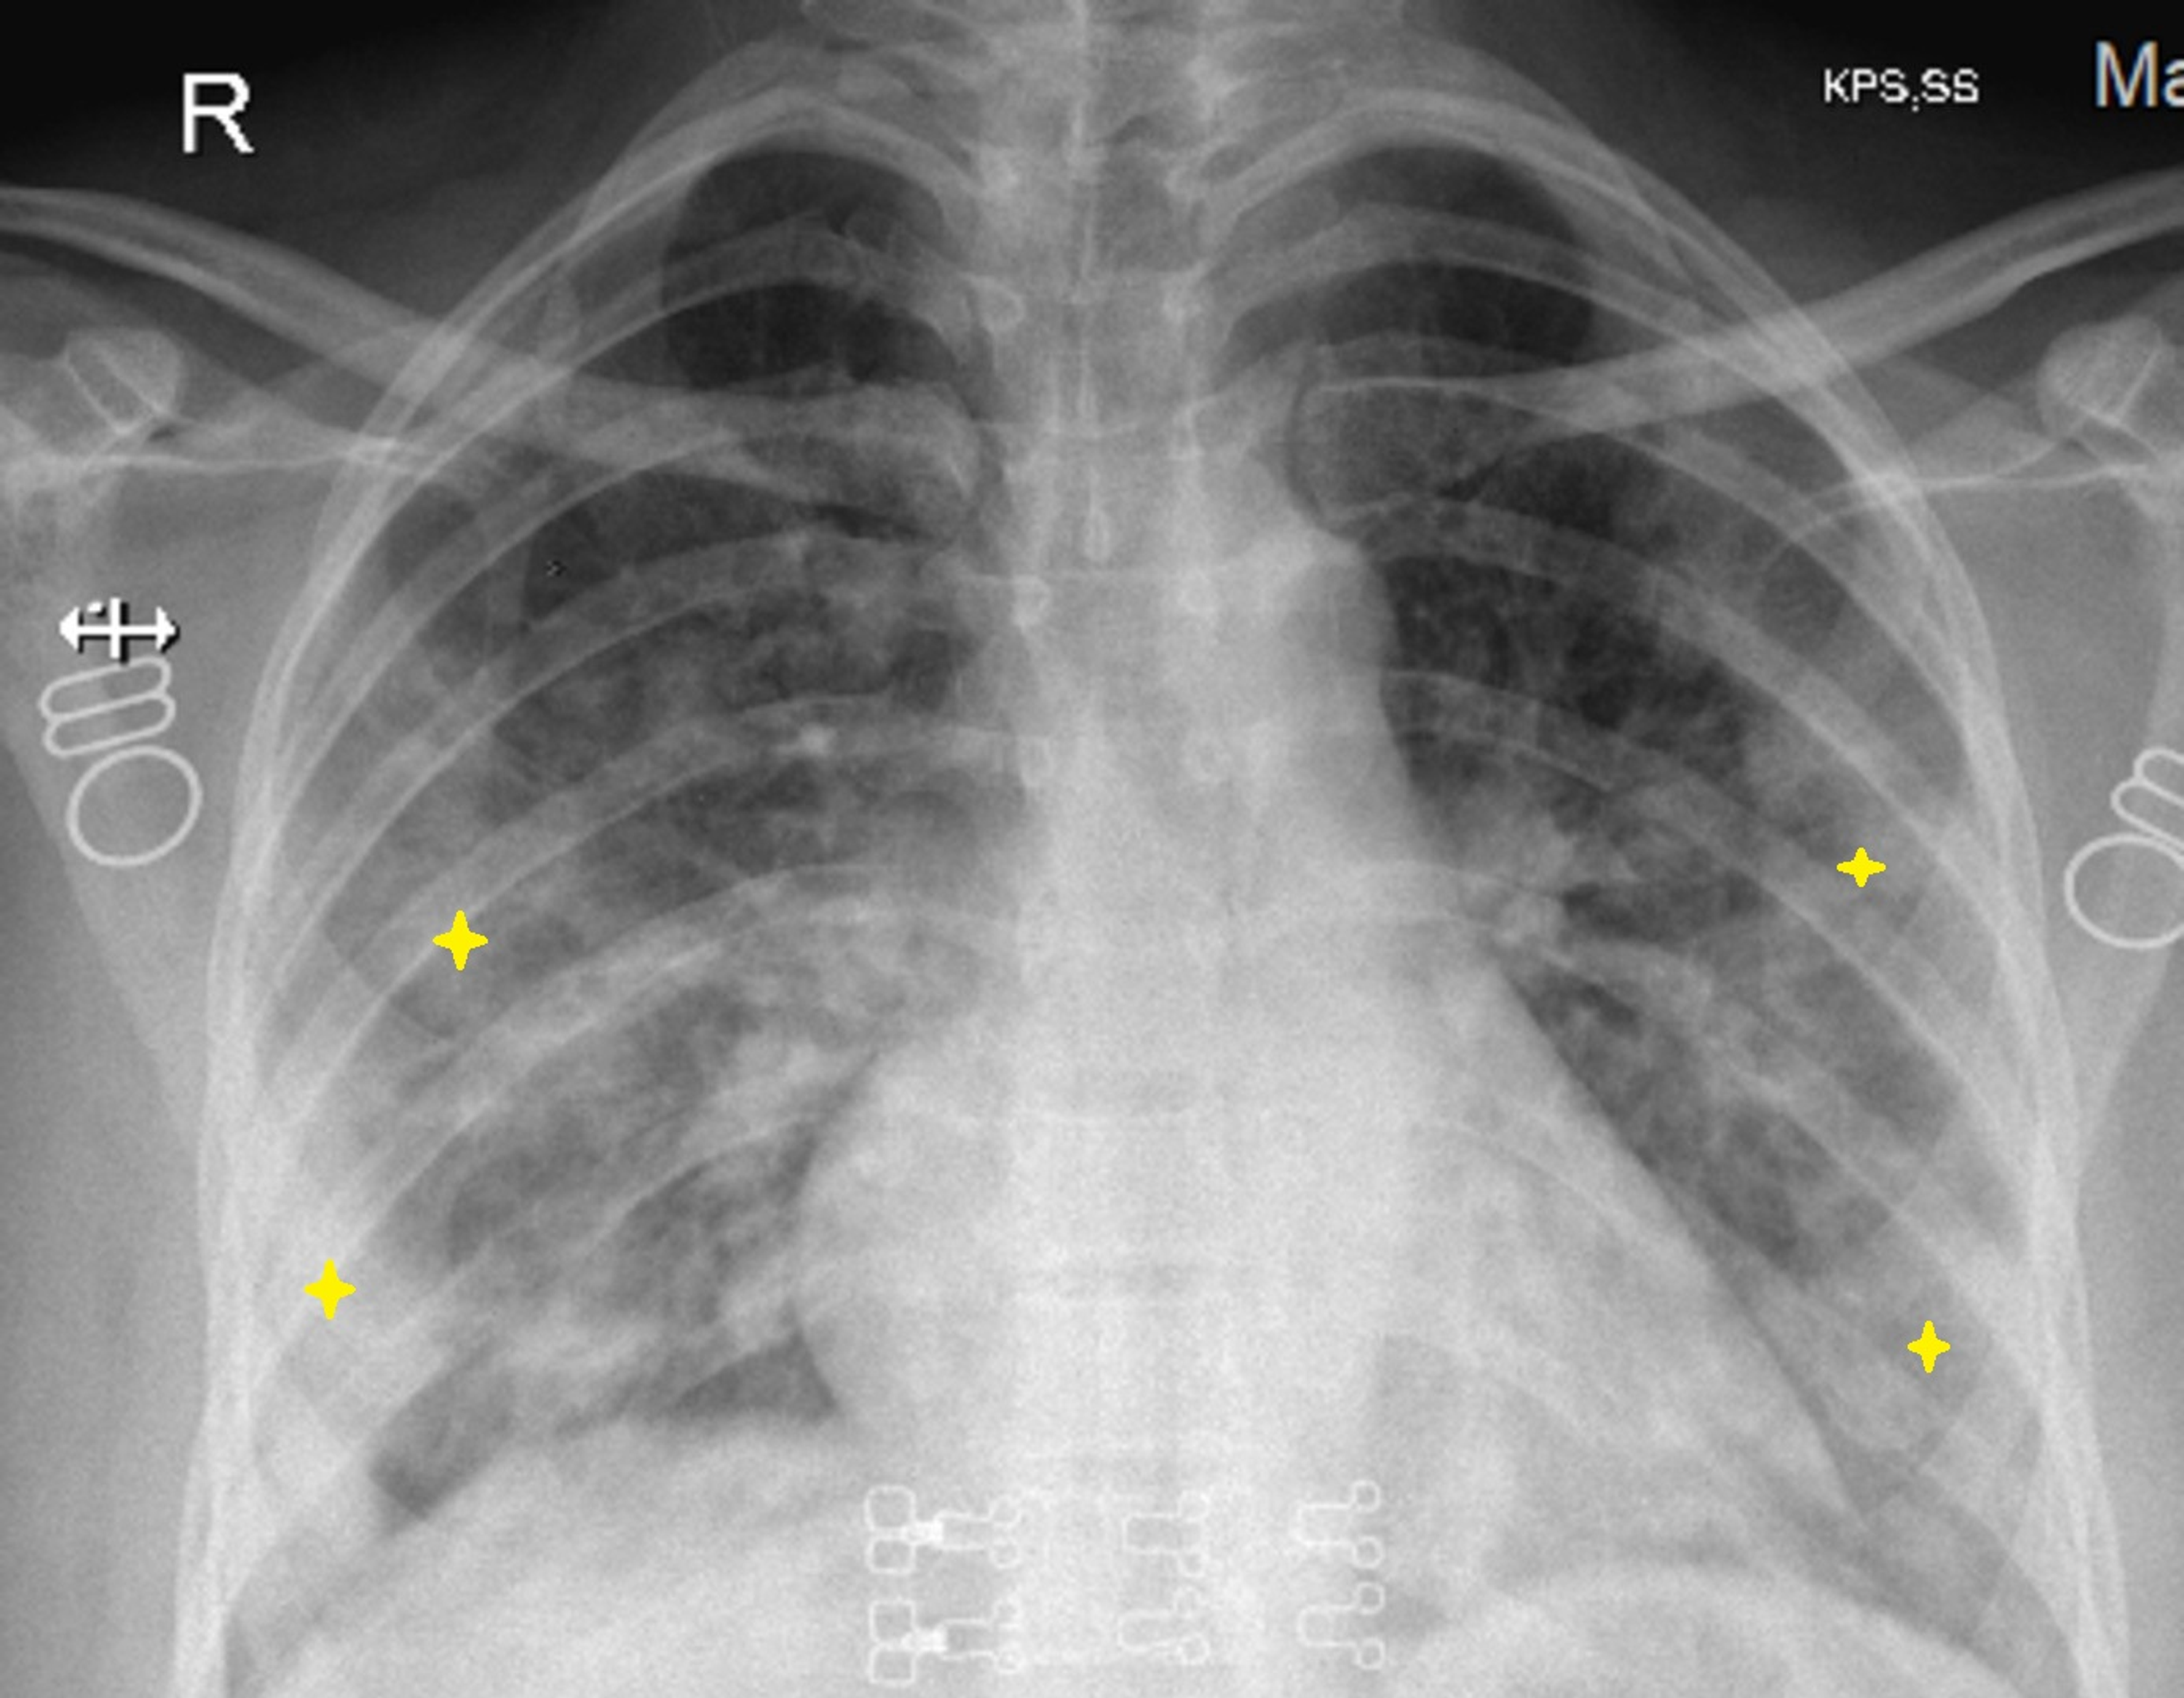

Covid 19 Pneumonia And Covid 19 Associated Acute Respiratory Distress Syndrome Diagnosis And Management The Pharmaceutical Journal